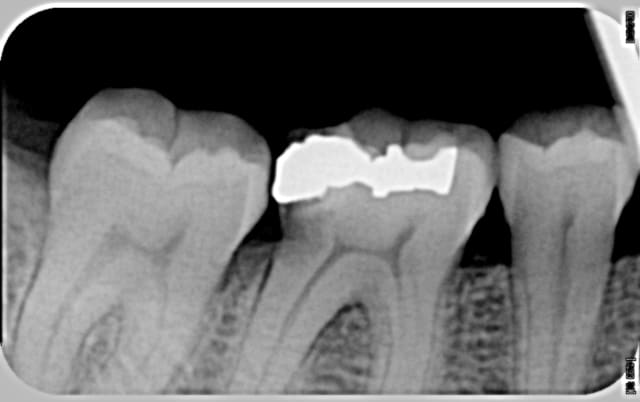

à votre avis, quelle est la lésion visible en distal de cette 46, qui semble descendre dangereusement dans la racine ?

La logique voudrait que ce soit une carie mais ...

Légère sensibilité au froid, rien de plus.

Ta radio me fait plus penser à une carie qu'à une résorption externe.

Carie! Due à l'absence de point contact... Dévitalisation, élongation coronaire puis couronne.

exo et implant oui malheureusement, comment restaurer une carie sous le niveau osseux avec une furcation très près??